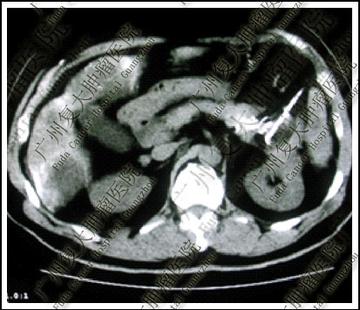

示意圖與當事人無關,來源:今日頭條,下全同